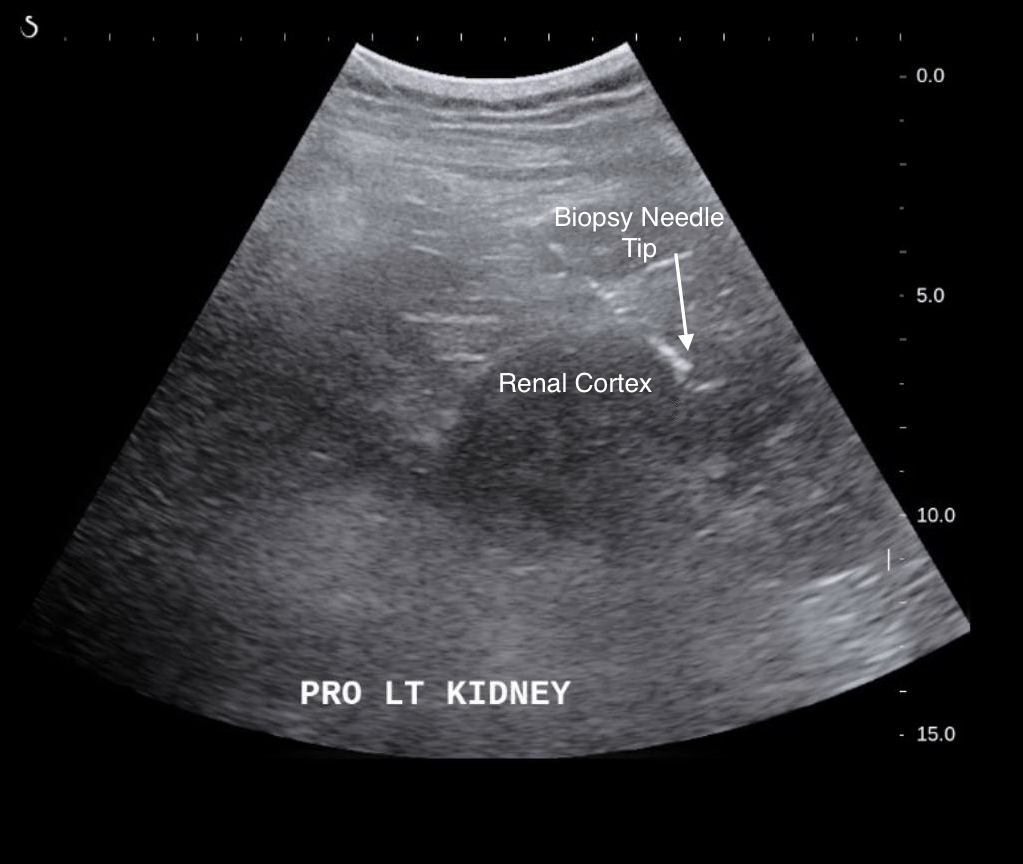

Kidney Biopsy Indications, Preparation and Procedure Kidney Biopsy Right Or Left a kidney biopsy typically involves a healthcare provider taking small samples of kidney tissue by inserting a thin, hollow needle through your back and into one or both kidneys. a kidney biopsy is a procedure in which a medical provider removes a small sample of your kidney tissue to examine it for signs of. a kidney biopsy. Kidney Biopsy Right Or Left.

ImagingGuided Percutaneous Renal Biopsy Rationale and Approach AJR Kidney Biopsy Right Or Left a kidney biopsy, also called a renal biopsy, is a procedure that is used to obtain small pieces of kidney tissue to look. However, there are other kidney biopsy techniques. Find out the reason for poor kidney function. a kidney biopsy is a procedure in which a health care professional takes one or more tiny pieces of tissue. Kidney Biopsy Right Or Left.

Interventional Radiology Procedures Ultrasound Guided NonFocal Renal Biopsy Stepwards Kidney Biopsy Right Or Left a kidney biopsy is a procedure in which a medical provider removes a small sample of your kidney tissue to examine it for signs of. However, there are other kidney biopsy techniques. Why do health care professionals use kidney biopsy? a kidney biopsy removes a small tissue sample to diagnose kidney disease or assess transplant function, using a. Kidney Biopsy Right Or Left.